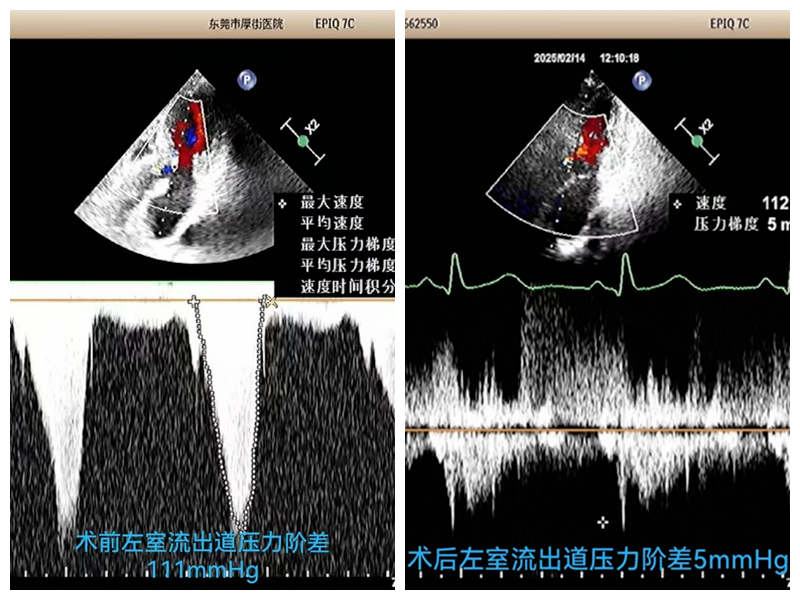

终于,在经过2个小时的紧张操作后,手术成功完成!唐阿姨的左室流出道压力阶差从111mmHg降至5mmHg,血流速度从526cm/s降至148cm/s,手术效果立竿见影。术后,唐阿姨被转入CCU监护病房,生命体征平稳。当她醒来时,发现自己不再胸闷气短,呼吸也变得顺畅起来。那一刻,她的眼中充满了感激的泪水。